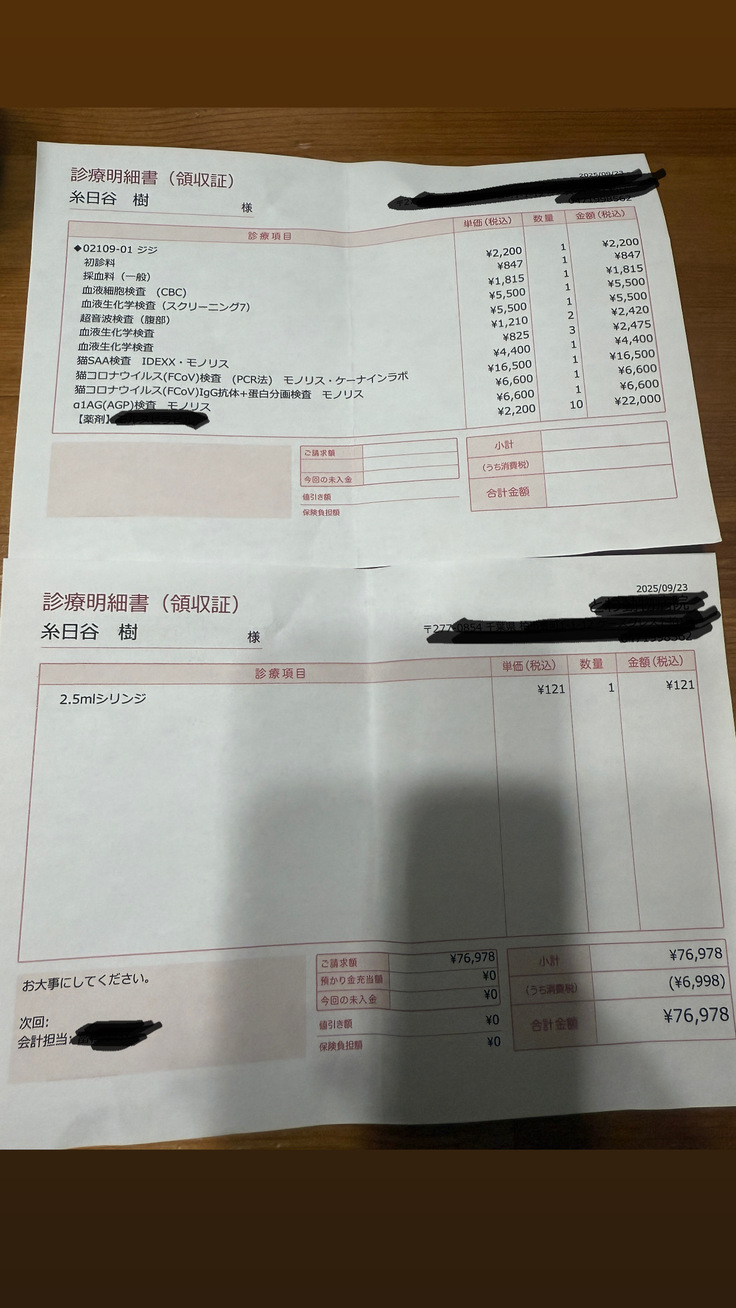

現時点までの治療費です⬇️

診察代、検査代、薬代の合計で210.386円

9/23▶️76.978円

9/27▶️17.105円